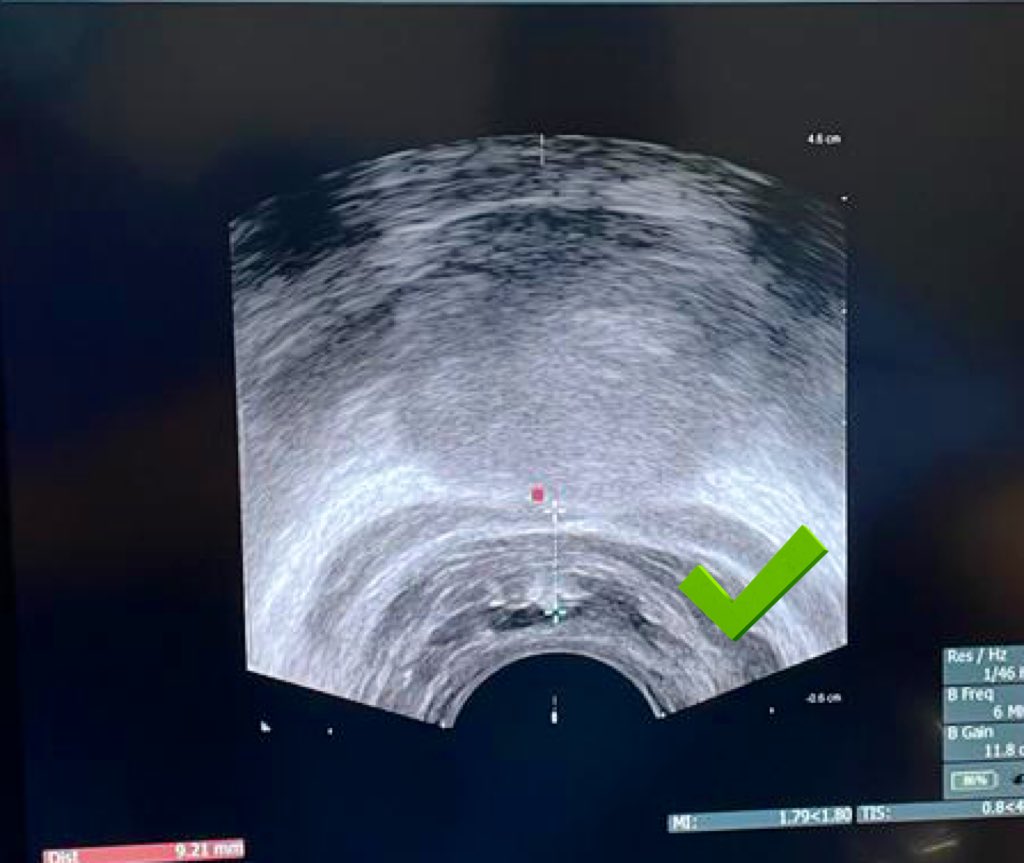

#SpaceOAR 👉🏽👉🏽 prevención de proctitis post-radiación #prostatacancer 👀 adecuada separación del recto @omarvic18 @EIvanBravoC @erenhu_gonzalez